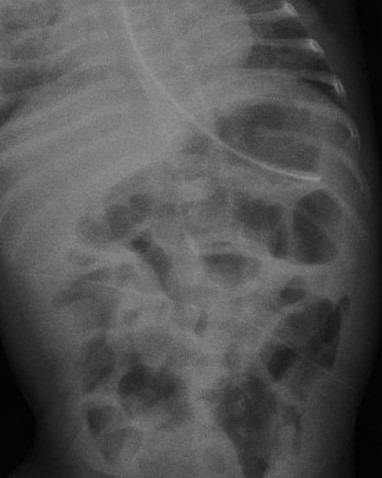

On day 128, he was noted to have abdominal distension, apnea, and non-bilious vomiting. C-reactive protein (CRP) was slightly raised but his abdominal X-ray showed gastric pneumatosis and dilated intestinal loops (Fig. 1). Septic work including blood and urine culture were sent and antibiotics commenced, supplemental nasal O2 was started. At the time of developing gastric pneumatosis the baby was on low birth weight formula feeds via nasogastric tube.

The condition can be easily diagnosed on plain X-rays of the abdomen. Rarely other diagnostic modalities are required. [1], [5] In gastric pneumatosis, the gas pattern noted in the X-ray appears as linear streaks of gas around a distended stomach and along the intestine [12], similar to our case. The condition is treated conservatively with gastric decompression, antibiotics, and withholding of feeds. Surgical management is reserved for gastric perforation or necrosis. Gastric emphysema often resolves with conservative treatment, which has a better prognosis than emphysematous gastritis. In our case, conservative therapy resulted in good outcomes.

Figure 1

X-ray abdomen showing gastric pneumatosis.